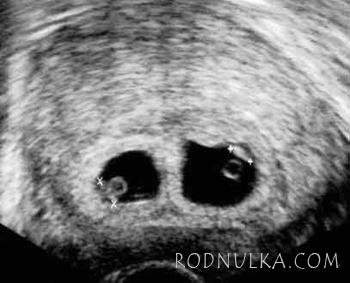

Перед вами — классическая двойня…